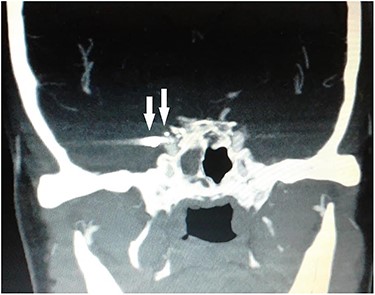

Computed tomography (CT) of the paranasal sinuses and angiography were requested on an urgent basis, which confirmed a diagnosis of pseudoaneurysm in her right CCA, adjacent to retained pellets (Figs 1–4). Also, her hemoglobin dropped from 11.5 to 8.4 gm over a 6-month period. Afterwards, she was referred to the interventional radiology department. She underwent stenting and coiling of her right internal carotid artery after which no further epistaxis happened for an uneventful year of follow-up.

CT scan coronal view showing gun pellets near the right cavernous carotid artery (arrows).